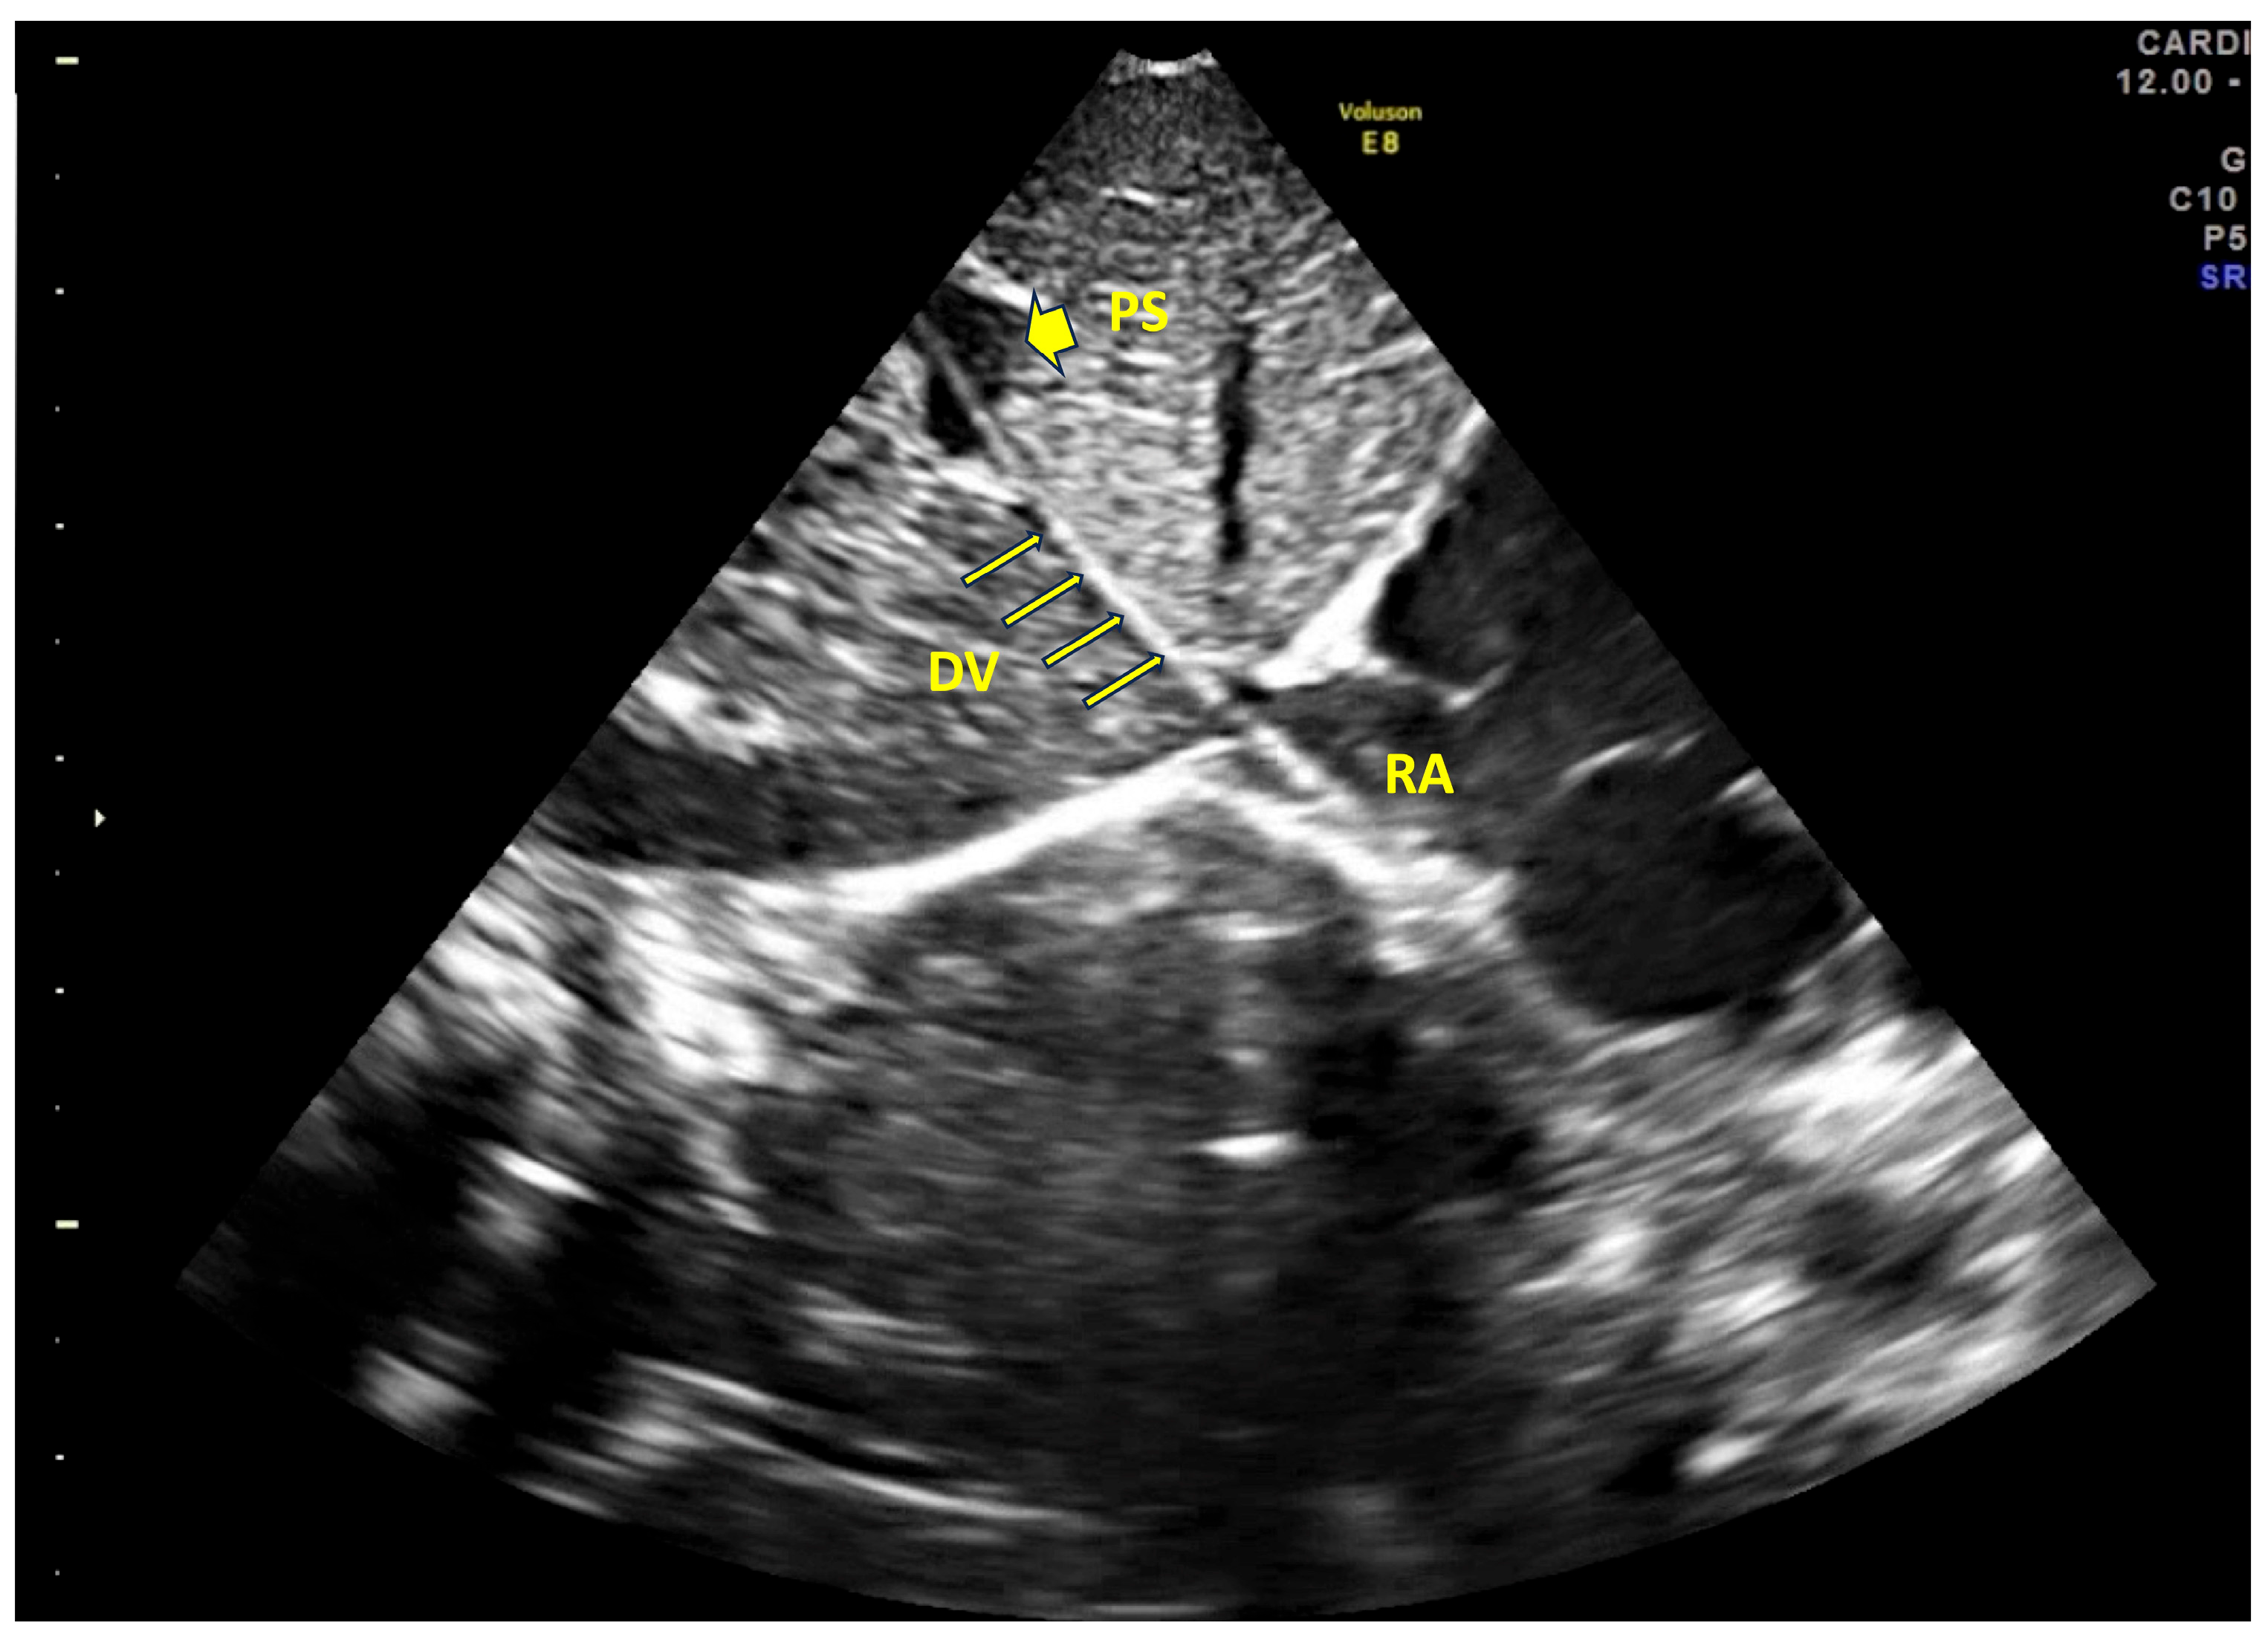

- Real-time tip navigation and tip location by US (according to the NeoECHOTIP protocol [17])

- Barone, G.; Pittiruti, M.; Biasucci, D.G.; Elisei, D.; Iacobone, E.; La Greca, A.; Zito Marinosci, G.; D’Andrea, V. Neo-ECHOTIP: A structured protocol for ultrasound-based tip navigation and tip location during placement of central venous access devices in neonates. J. Vasc. Access 2022, 23, 679–688. [Google Scholar] [CrossRef]

- Kishigami, M.; Shimokaze, T.; Enomoto, M.; Shibasaki, J.; Toyoshima, K. Ultrasound-Guided Umbilical Venous Catheter Insertion with Alignment of the Umbilical Vein and Ductus Venosus. J. Ultrasound Med. 2020, 39, 379–383. [Google Scholar] [CrossRef]